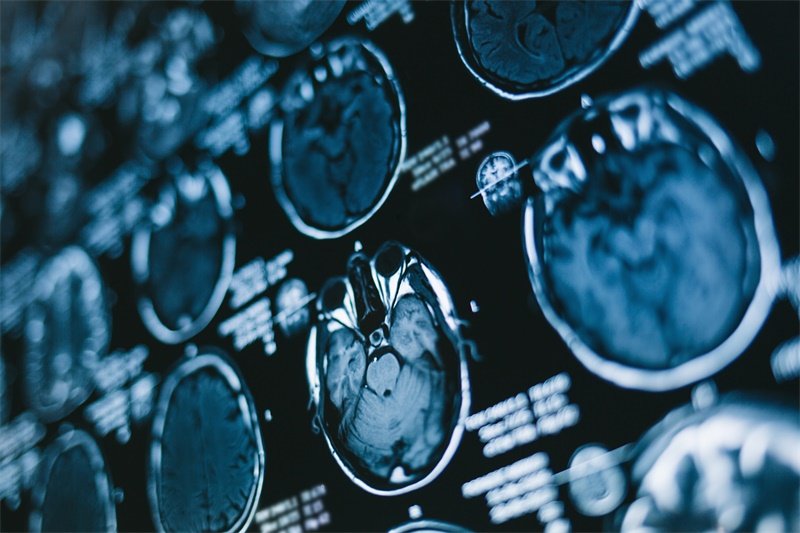

不同于一般脑肿瘤,枕部大脑左镰旁结节占位的发生可能与诸多因素相关,包括遗传、环境及病理状态等。因此,对于该结节的研究不仅要聚焦其影像表现,还需结合病患者的临床历史和症状。影像学检查,尤其是MRI(磁共振成像)是评估这一病变首选的方法,能够提供高分辨率的脑组织图像,帮助医生做出准确的诊断。

在MRI影像上,枕部大脑左镰旁的结节通常表现为高信号强度或混合信号,根据其成分的不同而有所变化。肿块可能呈现均匀或不均匀的信号,伴随的水肿或病理改变也会显现。在评估这些结节时,医生通常会考虑其位置、边界、信号特征及伴随症状。

例如,若结节具有明显的边界且信号均匀,则可能倾向于良性病变,如胶质瘤。而若结节边界模糊、信号不规则,则可能提示恶性病变或转移性病变。此时,为了更好地判断病变性质,可能需要进行进一步的影像学检查,如CT或者增强MRI。

在CT扫描中,枕部大脑左镰旁结节占位同样可以呈现为低密度或高密度影像,取决于其组织成分。CT的优势在于快速、便捷,能够用于急性情况下的初步筛查。此外,CT对钙化的识别能力优于MRI,对于判断结节的性质有一定的帮助。

然而,由于CT的软组织分辨率相对较低,可能会错过一些细小病变。因此,CT与MRI结合使用,能够更全面地评估病变,提供更准确的诊断信息。